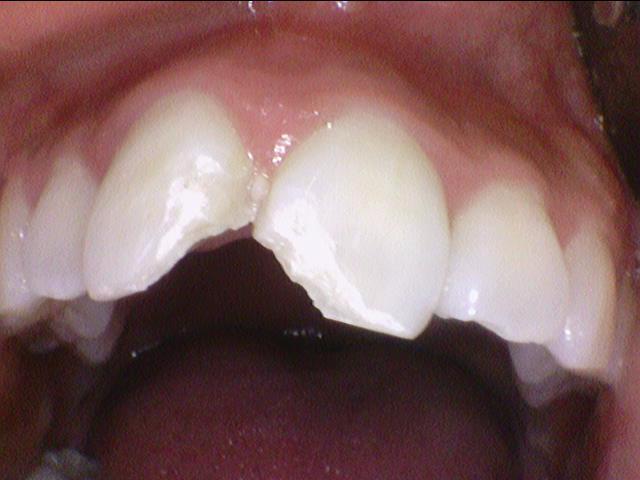

놀다가? 넘어져서 치아가 부러진 외국인 환자분입니다.

입술에도 상처가 나 있는 걸 볼 수 있습니다.

레진으로 떼우면 아래 치아와 닿아서 많이 떨어질 가능성이 있지만

다음달 본인 나라로 출국 예정이라 라미네이트 생각이 있긴 한데

지금은 급하게 레진으로 떼우고

본인 나라에서 원래 주치의와 다시 상담하기로 하고 레진으로 떼워드렸습니다.